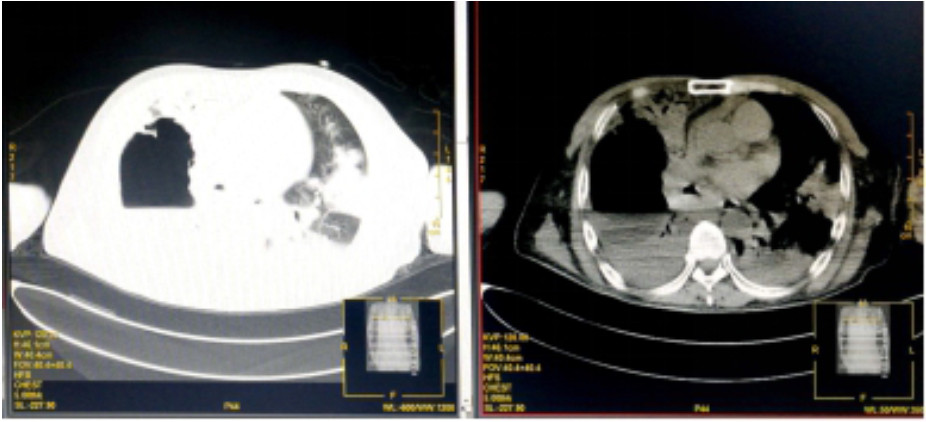

入院诊断“社区获得性肺炎”。予无创呼吸机支持(FiO2 75%),经验性予以美罗培南静脉泵入1.0 g 2次/d、磷酸奥司他韦口服75 mg 2次/d、莫西沙星静脉滴注0.4 g 1次/d。入科后治疗4 h仍无尿,且呼吸困难进行性加重,血氧饱和度进行性下降,氧合指数109 mmHg,予以经口气管插管接呼吸机辅助通气及连续性血液净化等治疗。机械通气后,吸出大量灰褐色痰,且病情进展快,短时间无法脱机拔管,12月17日气管切开。12月17日复查血常规:血白细胞2.49×109/L,中性粒细胞百分比0.925,血红蛋白70 g/L,血小板62×109/L。停用莫西沙星改用利奈唑胺0.6 g静脉滴注2次/d。12月19日胸部CT示,⑴双肺散在多发感染性病变,右侧为著;⑵右肺空腔伴气液平;⑶右侧胸腔积液(图 2)。12月19日血白细胞3.7×109/L,中性粒细胞百分比0.882,淋巴细胞百分比0.098,血红蛋白78 g/L,血小板115×109/L,入科后立即送检的血、痰培养回报均阴性。12月20日肺泡灌洗液病理回报镜下见炎症细胞、吞噬细胞及菌丝样物,未发现恶性细胞(图 3)。12月21日痰宏基因组学检测回报:肺炎链球菌(序列数113 916)、屎肠球菌(序列数1 307)、铜绿假单胞菌(序列数16)。12月20日及24日肺泡灌洗液、血培养均回报为屎肠球菌,药敏试验结果示,对氨苄青霉素、环丙沙星、红霉素、庆大霉素、青霉素耐药;对替考拉宁、替加环素、利奈唑胺、万古霉素、奎奴普丁/达福普丁敏感。继续利奈唑胺600 mg 2次/d,总疗程62 d。治疗期间血红蛋白在66~91 g/L,血小板均在(100~300)×109/L。12月26日CT引导下经皮肺组织穿刺术,并送检病理细胞学及组织培养,结果显示符合炎症性病变改变,病原学阴性。2020年1月9日脱离呼吸机,1月14日转入普通病房,1月23日拔出气管切开套管,2020年2月13日复查胸部CT病灶有所吸收(图 4),2月24日好转出院。出院半年后电话随访,当地医院复查胸部CT示病灶较前明显吸收,已经正常工作。

| 图 2 患者2019年12月19日胸部CT结果(双肺散在多发感染性病变,右侧为著;右肺空洞伴气液平面;右侧胸腔积液) |